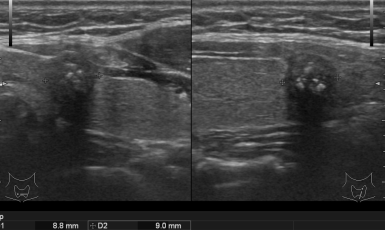

303번째 갑상선암 진단사례 (2019년5월23일) 목 앞쪽에 단단한 혹이 만져지고 불편감이 있어 진료위해 내원해 주신 환자분이셨습니다. 진찰상 앞쪽 목, 즉 오른쪽 갑상선..

302번째 갑상선암 진단사례 (2019년5월20일) 몇주전부터 목이 불편하고 삼킬때마다 통증이 있어 갑상선 관련 질환인지 확인하기 위해 저희 병원에 내원해 주신 환자분이셨습니..

301번째 갑상선암 진단사례 (2019년4월8일) 갑상선과 관련된 특별한 증상없이 왼쪽 겨드랑이 통증을 주소로 내원해 주신 환자분이셨습니다. 유방 초음파상 ..